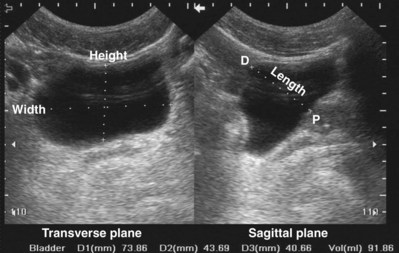

Figure 4–34 A, Transverse view of the bladder in this female patient demonstrates the uterus (U). B, Sagittal view of the bladder shows the uterus posterior to the bladder.

Figure 4–35 In this transverse view of the bladder, urine “jets” emerging from the left (arrow) and right (arrowhead) ureteral orifices are demonstrated by power Doppler.

Bladder volume can be calculated manually by obtaining measurements in the midtransverse and midsagittal planes (Fig. 4–36). Numerous studies have shown that for bladder volumes between 100 and 500 mL, such calculated volumes are within 10% to 20% of the actual bladder volume (Roehrborn et al, 1986).